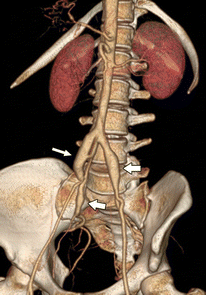

Vascular EDS Photo Gallery

Pictures of vascular EDS and its symptoms